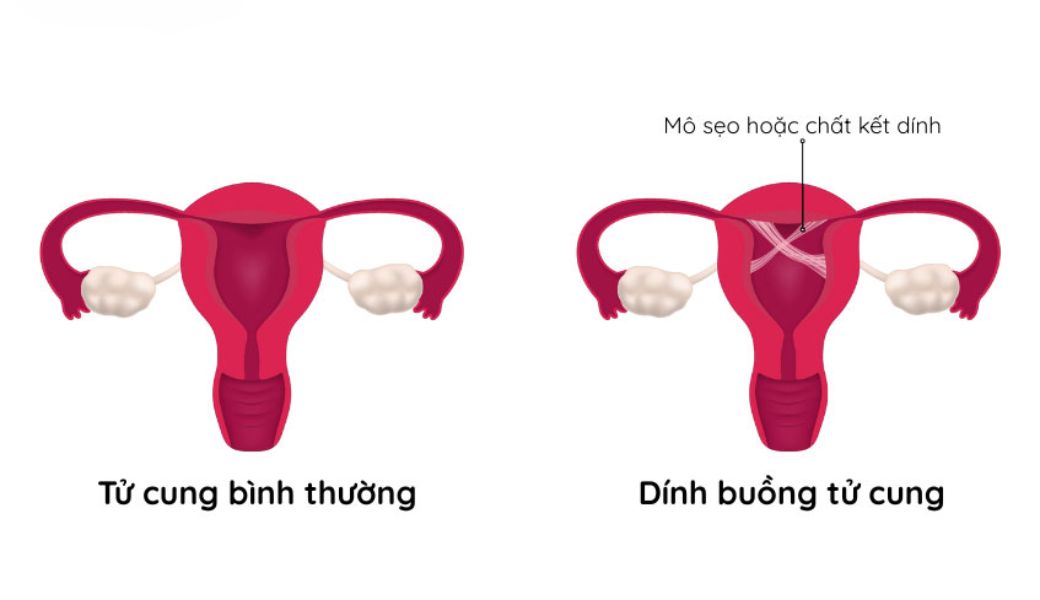

Dính buồng tử cung, hay còn gọi là hội chứng Asherman, là tình trạng hình thành các dải sẹo hoặc mô liên kết bất thường bên trong buồng tử cung. Những dải dính này có thể là màng mỏng hoặc dải sẹo dày, chia buồng tử cung thành nhiều ngăn nhỏ.

Trong điều kiện bình thường, thành trong của tử cung được phủ bởi lớp nội mạc tử cung mềm mại. Khi bị tổn thương, lớp nội mạc này có thể lành sẹo và dính lại với nhau, tạo thành những cầu nối bất thường.